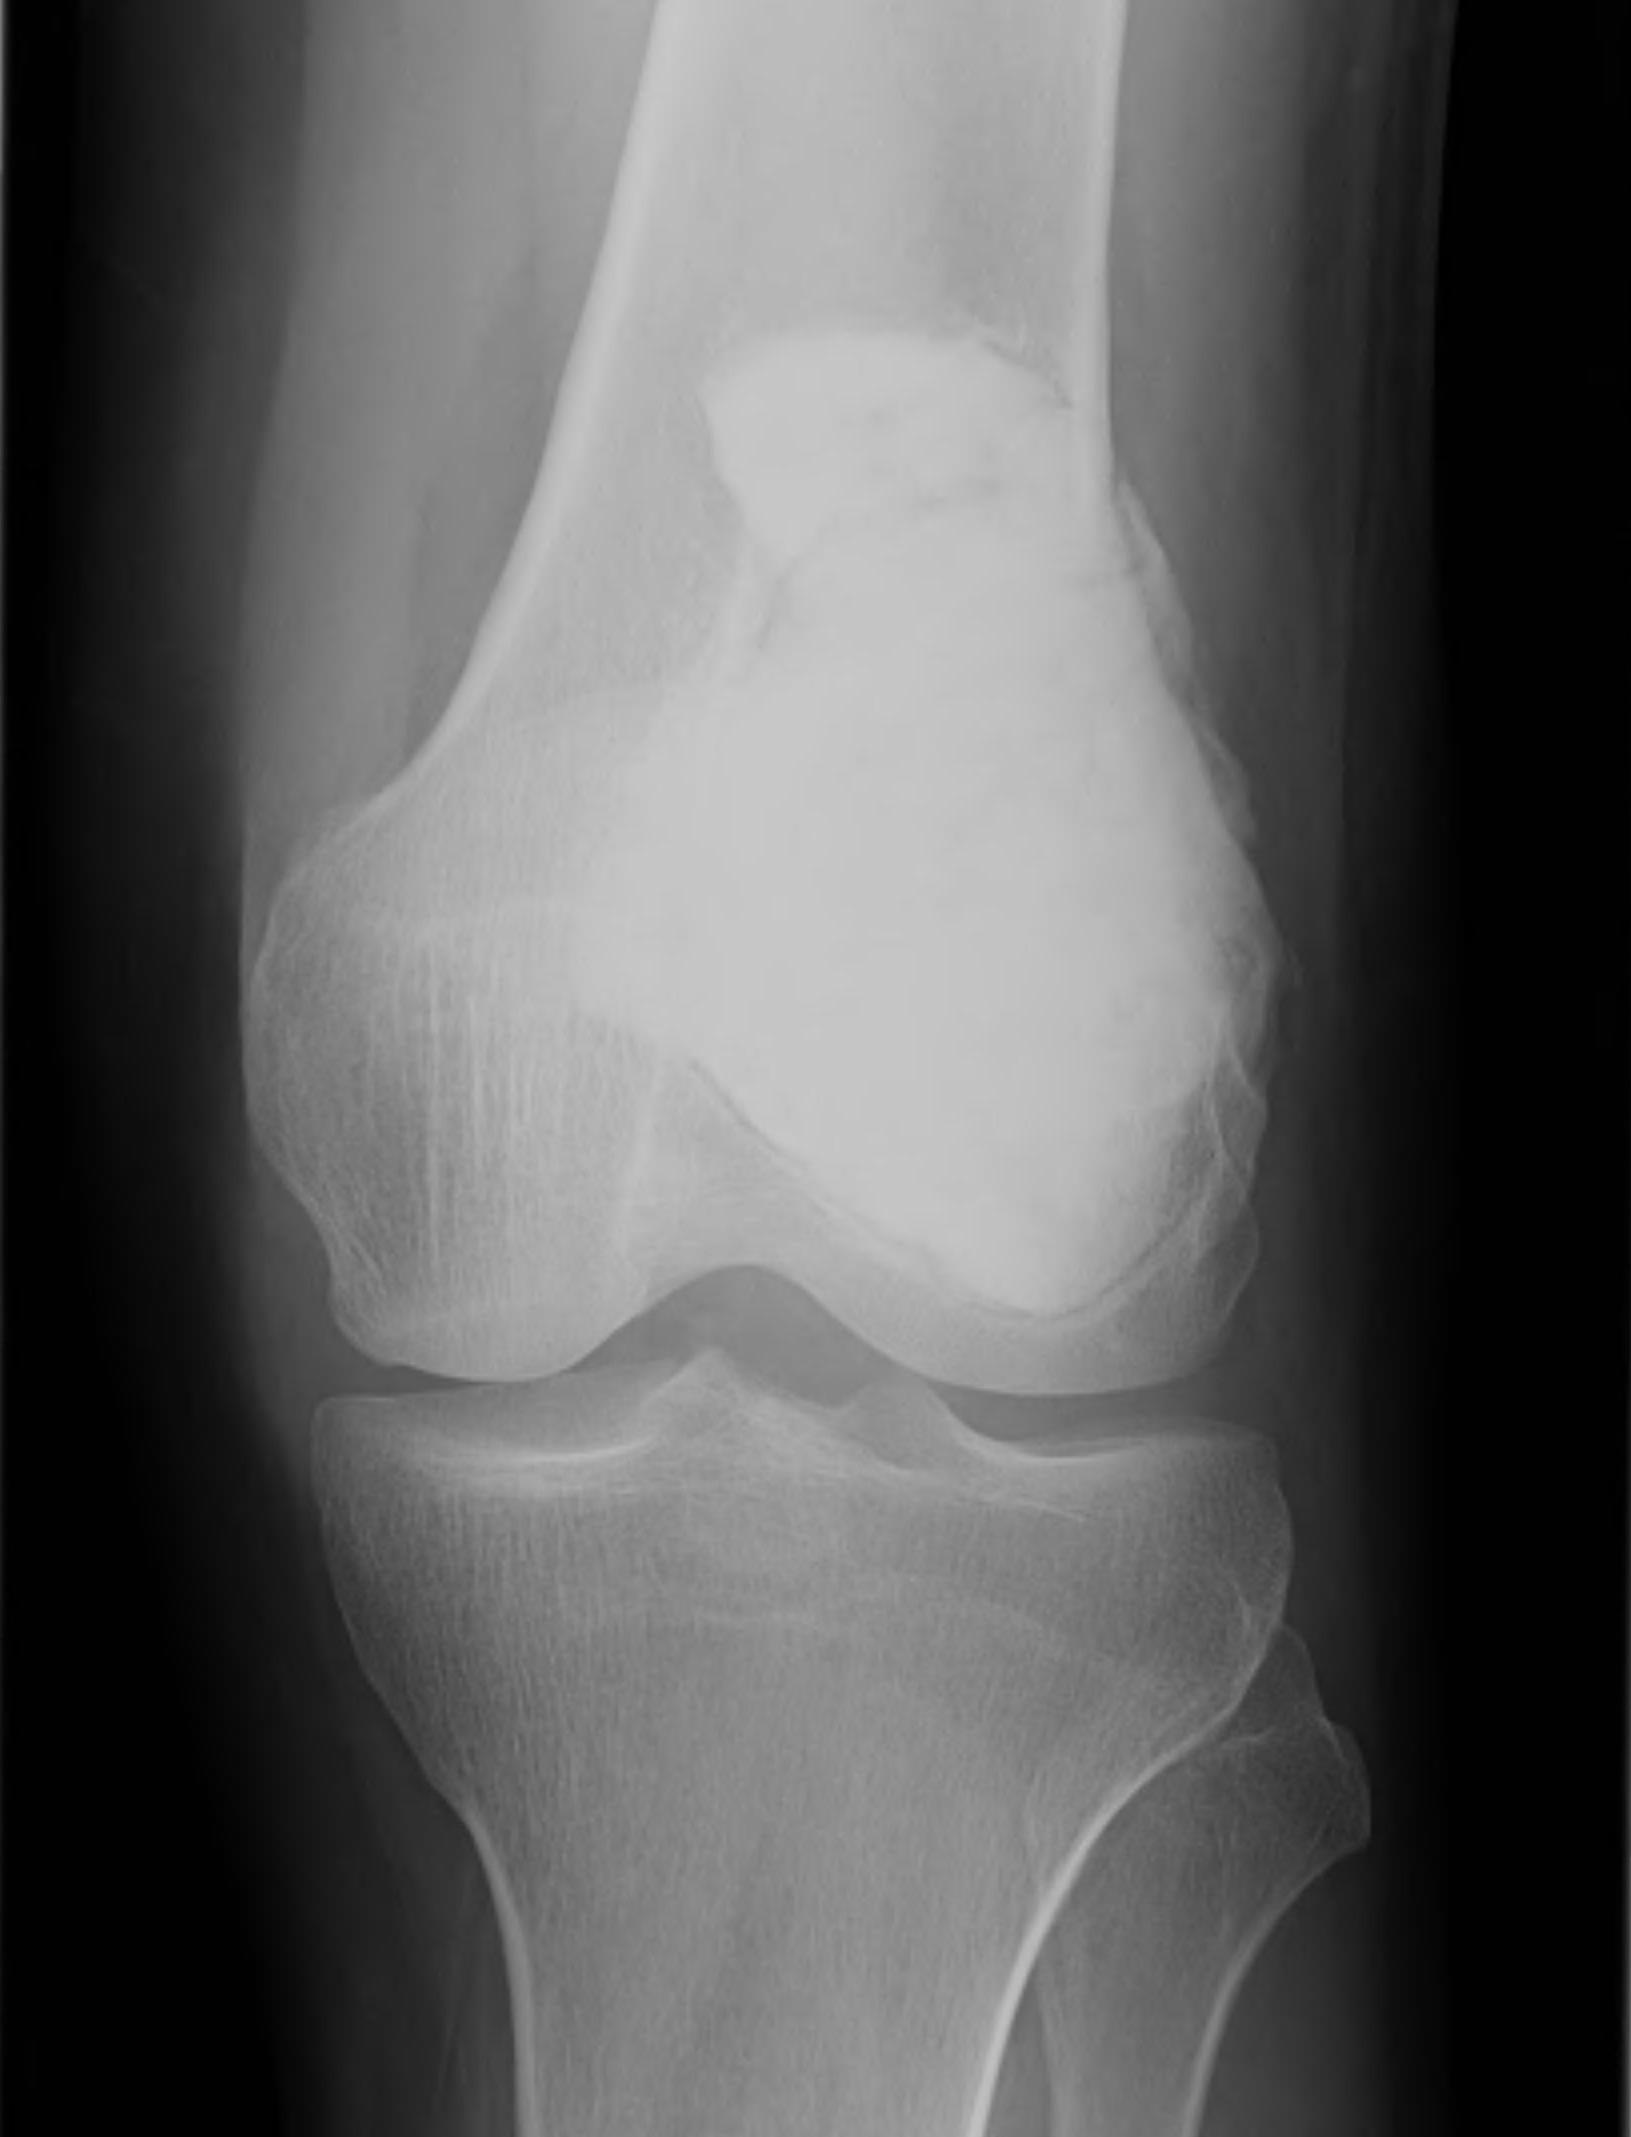

X-ray

Eccentric, sharply demarcated lytic lesion

- no sclerosis around lesion

- narrow zone of transition

- metaphysis, extending into epiphysis

- no mineralization

Expanded cortex but no breakthrough Symptomatic Often have pathological fracture Active on bone scan Histologically benign |

Rapidly growing mass Cortical perforation, soft tissue mass Symptomatic Extensive activity on bone scan Histologically benign |

85% meta-epiphysis of long bones